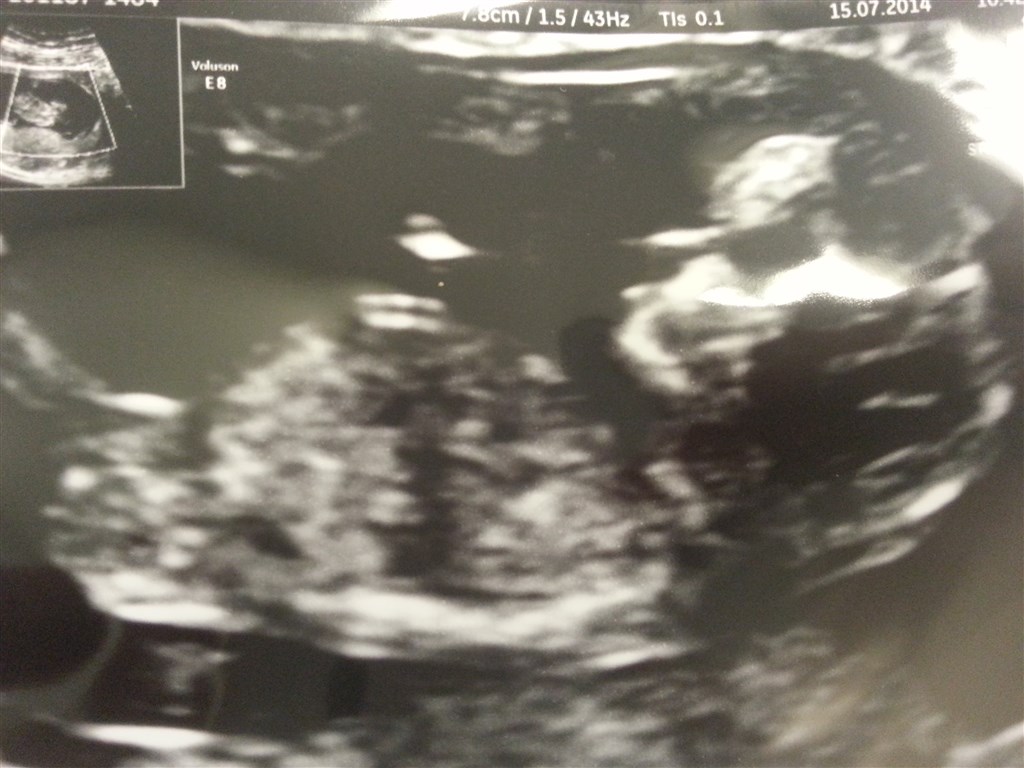

så er NF som overskriften siger overstået og vores lille baby har det super godt.. den ville ikke rigtig være med til at blive taget billeder af så der måtte rystes lidt numse og så gik det fint

Vedhæftede fotos (klik for at se i fuld størrelse)